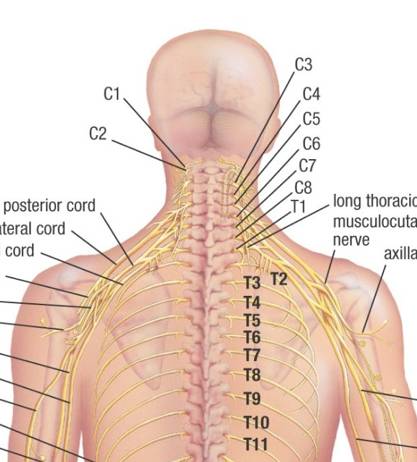

The Back Wound

In the autopsy photograph (Appendix 5, Figure 2), the back wound appears to lie at about T1 (i.e., the first thoracic vertebra), just above the level of the scapular spine. This seriously disagrees with the T3 on the death certificate, which was prepared by Admiral Burkley (p. 221). Two individuals even placed it at T4: James Jenkins and, in a conversation with me, John Ebersole (who practiced my specialty of radiation oncology). For normal anatomy see Appendix 5, Figures 3A and 3B. As is well known, the back wound in the autopsy photo is noticeably higher than the holes in the shirt or jacket. Furthermore, the wound on the Autopsy Descriptive Sheet (prepared by Boswell at the autopsy; see Appendix 5, Figure 4) appears to lie well below T1—at least as low as T2, if not even lower. An online source assigns a typical level to the scapular spine as T3 (manualmed.blogspot.com/2008/09/thoracic–spine-landmarks.html). In fact, any level for this back wound below T1 would destroy the SBT (because the back wound would then be lower than the throat wound). However, Boswell later elevated this wound, thus abandoning his earlier, on-site observation. Somewhat amusingly, on this second occasion Boswell elevated this back wound far too high (compared to the autopsy photo), actually into the neck, which only raises questions about either his memory or his honesty. (See these two incompatible placements by Boswell at Inside the ARRB by Douglas Horne, Volume I, Figure 56.) A likely explanation for the discrepancy between the photo and the Descriptive Sheet is post-autopsy (illicit) photo alteration in the dark room. Curiously, this is the precise autopsy photo that displays an anomalous object on the back (not noted by prior investigations), which might be a leftover image from photographic tampering. Further discussion of this follows below.

Another point is worth emphasizing: physical tests showed no copper deposits on the shirt or on the collar (in the front), even though they were present on the back of JFK’s jacket. This is consistent with a metal projectile as the source for the back wound, but it is inconsistent with a metal projectile through the front of the shirt. On the contrary, the slits had probably been created by the nurses’ scalpels. In an interview in 1971, Carrico actually confirmed this to Harold Weisberg—see Weisberg’s Subject Index File, under “Carrico,” items 02 and 03. (Jerry McKnight reports this.) In addition, based on my personal observations at the Archives, some cloth is missing from both the back of the shirt and the back of the jacket, but none appears missing from the slits at the collar. Furthermore, although McAdams claims that a throat wound at C7/T1 is feasible, he totally ignores the anatomic conundrums in the horizontal plane. (For pertinent, and rather devastating, anatomy and radiology images see Appendix 5, Figures 5-7.) For a more precise vertical level for the throat wound see MIDP (p. 228). James H. Fetzer has also offered a concise analysis of this evidence in “Reasoning about Assassinations,” which he presented at Cambridge and then published in an international, peer-reviewed journal (The International Journal of the Humanities (2005-2006), Volume 3, Issue 10, pp. 31-40).